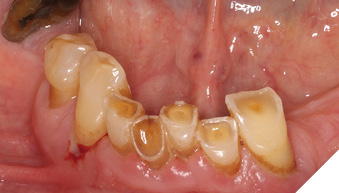

A 65-year-old woman comes to the office with the chief complaint of worn-down teeth, missing teeth, tooth sensitivity, especially on maxillary teeth and TMJ pain. Her past medical history was reviewed and was significant for asthma, insomnia, hypercholesterolemia, hypothyroidism, and anxiety disorder. She denied any sleep disturbances. Her medications included salbutamol, ezetimibe, quetiapine, and levothyroxine. She referred to being allergic to dust and shellfish and sensitive to propofol. She had a right mastectomy in 2014 due to breast cancer. No chemotherapy or radiation was done. Her diet was considered normal, and she denied any consumption of acidic drinks and denied any history of regurgitation. She denied any parafunctional habits during the day. She was using a maxillary transitional partial denture since she had lost some of her teeth due to fracture and caries. No other problems were evidenced. Intraoral exam showed moderate attrition lesions of posterior teeth, porcelain fused to metal crowns on teeth 46 and 47 had the porcelain portion worn down, exposing the metal substructure. Missing teeth included teeth 14,15,16,18,24,28, 36,38,48. Palatal surfaces of maxillary anterior teeth also appeared worn down. An abfraction lesion was found on tooth 23. No carious lesions were found in any of her teeth. Composite restorations on mandibular anterior teeth were chipped or were missing (Figs. 6-11) She also presented with limited mouth opening: 35 mm interincisal distance at maximum opening. There was bilateral pain on palpation of preauricular areas. Her pain was the worst early in the morning which suggested night parafunction. No crepitus, or joint clicking were found.

Fig. 6

Fig. 7

Fig. 8

Fig. 9

Fig. 10

Fig. 11